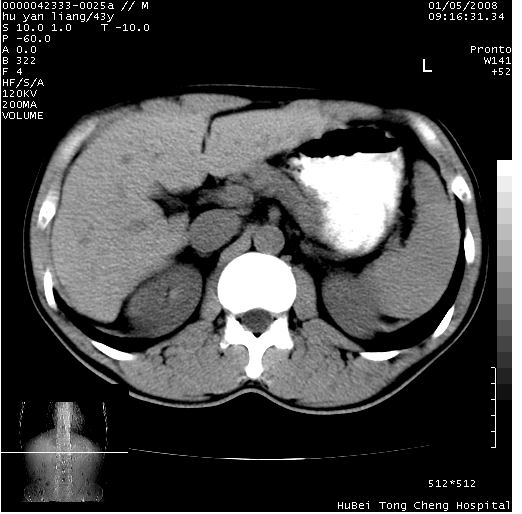

患者 男,43岁。右上腹不适1年余。既往有“肝右叶肝脓肿”病史,经保守治疗后痊愈。

b超提示:1)肝右叶肝内胆管结石。2)肝右叶占位性病变待排。

上中腹部ct轴位平扫+增强扫描(层厚10mm,螺距1.0,重建间隔10mm),图像如下:

肝右上叶偏后方较大团片状钙化灶,支持:肝脓肿后遗改变!

肝右叶后段团块状钙化灶,结合病史考虑肝脓肿痊愈后表现。